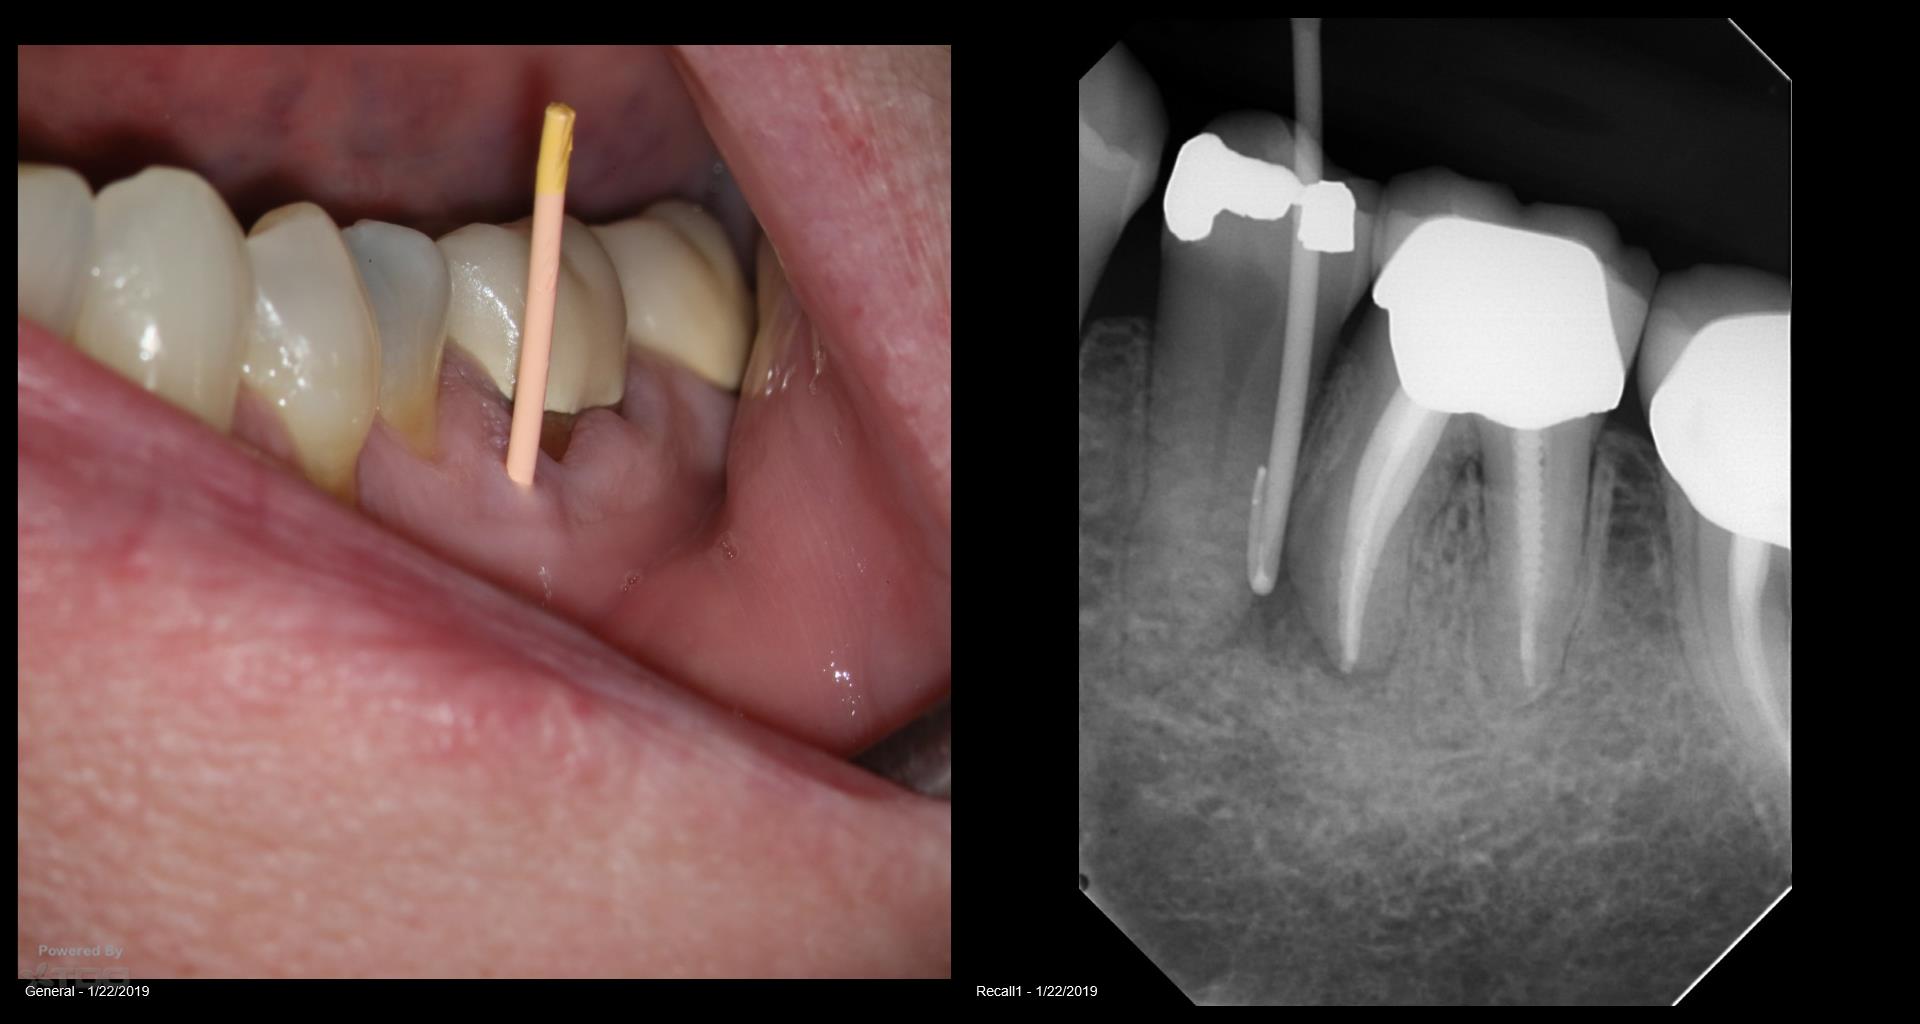

Patient in for a sinus tract check recall today asking questions…… All treatment done by endodontists. Always done in a single visit. The 2nd endodontist told the patient she was “cured”. He never checked her again. When she called and said she may have a problem… they told her it wasn’t necessary. Her GP told her to have it extracted. Is it fractured? Is it a failing RCT that can be saved? How does one tell? To me, to do a retreatment like this in a single visit….. Well…it isn’t the way I would like to be treated. Because you end up with cases like this. By the way: no symptoms. gbc